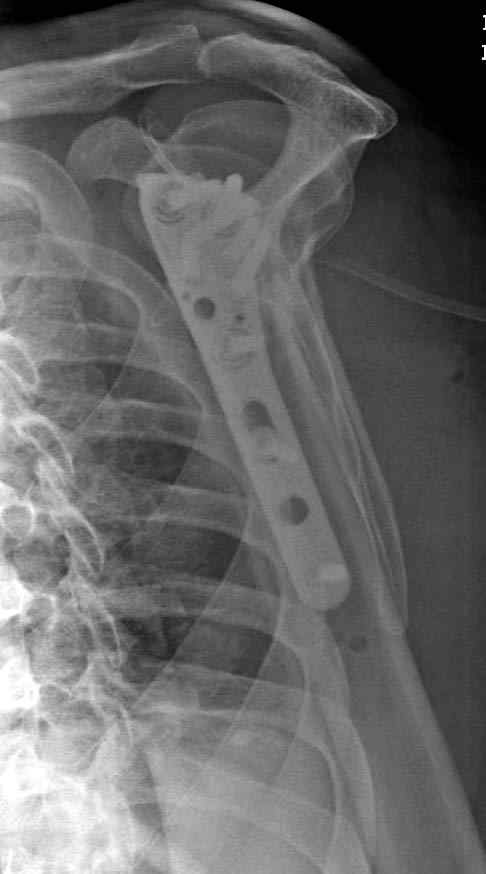

Здесь пример открытой репозиции 57 летнего с переломом плеча (1,2)  смещение обнаружено на  интероперационном снимке. При нормальной прямой проекция (3) угловое смещение обнаружили в аксиальной проекции (4)

После устранения смещения пластина установлена выше (5,6,7) и финальные снимки (8,9,10)